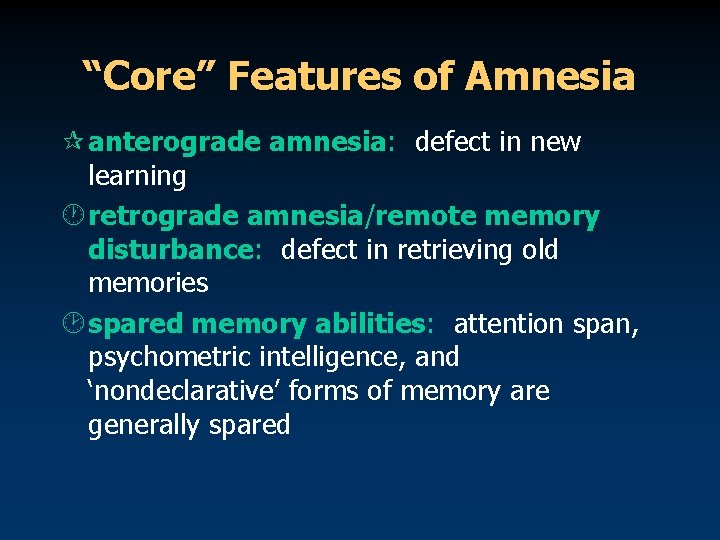

“Core” Features of Amnesia ¶ anterograde amnesia: defect in new learning · retrograde amnesia/remote memory disturbance: defect in retrieving old memories ¸ spared memory abilities: attention span, psychometric intelligence, and ‘nondeclarative’ forms of memory are generally spared